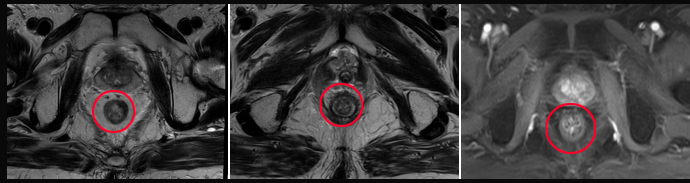

原发灶放疗靶区

原发灶治疗后

潞河医院放疗科自2019年开诊以来,陆续收治多例结直肠癌治疗初期或治疗过程中出现肺转移、肝转移,甚至脑转移的患者,立体定向放疗(SBRT)、大分割放疗等措施与手术、药物的有机结合,为这些患者再次争取到治愈的机会,使晚期的患者仍然可以争取到高质量的长期生存。